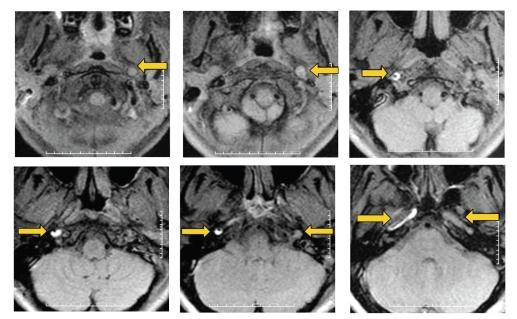

The challenge in acute stroke is still to reperfuse as early as possible the ischemic territory. Since fibrinolytic therapies have a limited window with potential risk of bleeding, having a nonpharmacologic mean to recruit vessels in area surrounding necrosis might be useful. We propose here to use antigravity suit inflated at "venous" pressure levels to shift blood towards thoracic and brain territories. We report two cases of spectacular clinical recovery after acute carotid occlusion.

急性中风的挑战仍然是尽早使缺血区域再灌注。由于纤维蛋白溶解疗法的时间窗有限且有潜在出血风险,采用一种非药物手段来促使坏死区域周围的血管恢复供血可能会有所帮助。我们在此提议使用在“静脉”压力水平充气的抗重力服,将血液转移至胸部和脑部区域。我们报告了两例急性颈动脉闭塞后临床症状显著恢复的病例。